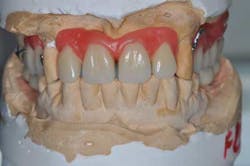

Figs. 7a, b, and c: Teeth and ceramic mounting